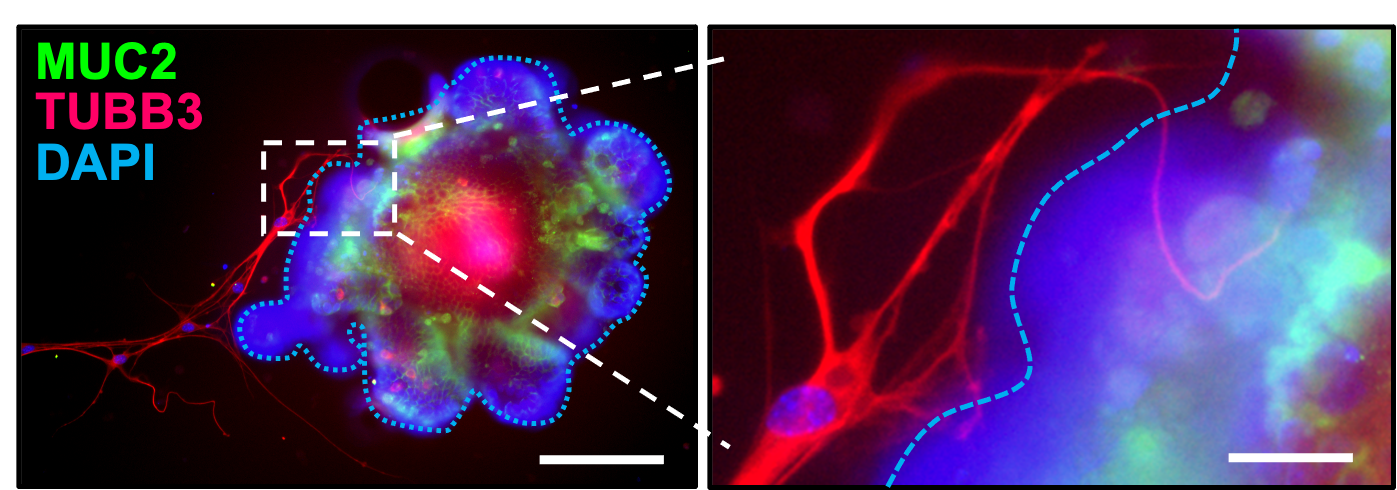

Intestinal IL6ST-Induced GAP Formation. Using genetic models with IEC-specific IL6ST activity either increased (gain-of-function) or decreased (loss-of-function), combined with a sophisticated co-culture system of small intestinal organoids and enteric neurons, we demonstrate that IL6ST/gp130 signaling promotes GAP formation through activation of the mAChR4 pathway.

Co-cultured mouse SI organoids with enteric neurons. Figure from Llorente et al., Nature, 2025 - mAChR4 Pathway Induction Prevents ALD. Activating mAChR4, chemogenetically, or via IL6ST signaling, restores this immune cascade circuit, reduces bacterial translocation, and prevents ethanol-induced steatohepatitis.